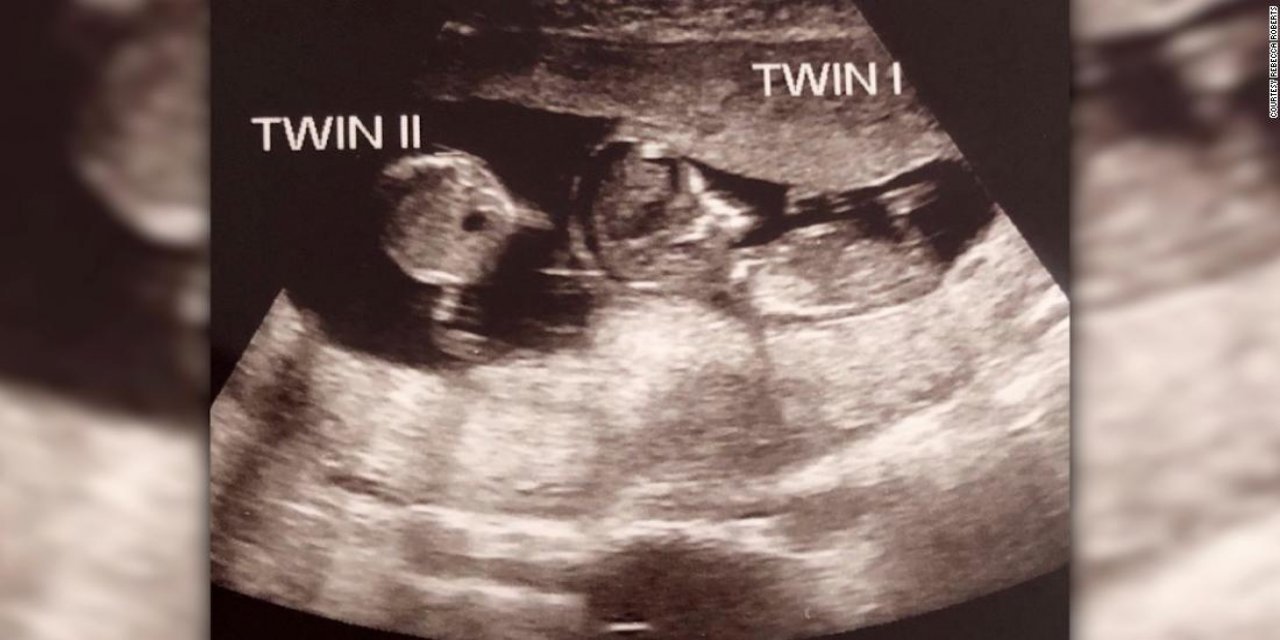

Hamileliğinin üçüncü ayında öğrendi! Hamileyken tekrar hamile kaldı!